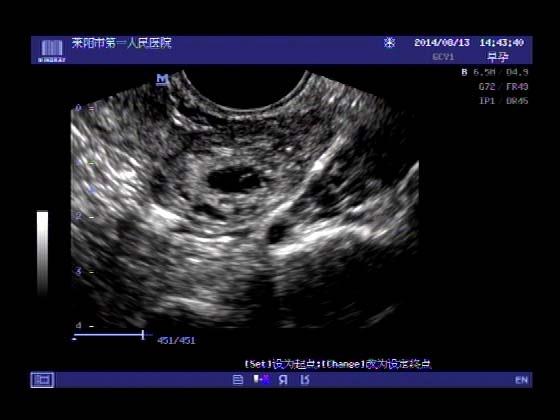

超声入门贴341:宫外孕(阴超的魅力)

女,32岁,停经15天,

一周前在上极医院检查:化验尿HCG阳性,血HCG400多,超声检查问见明显孕囊,让随访。

看见卵黄囊啦~孕囊型的吧?

还能看到卵黄囊,真不错